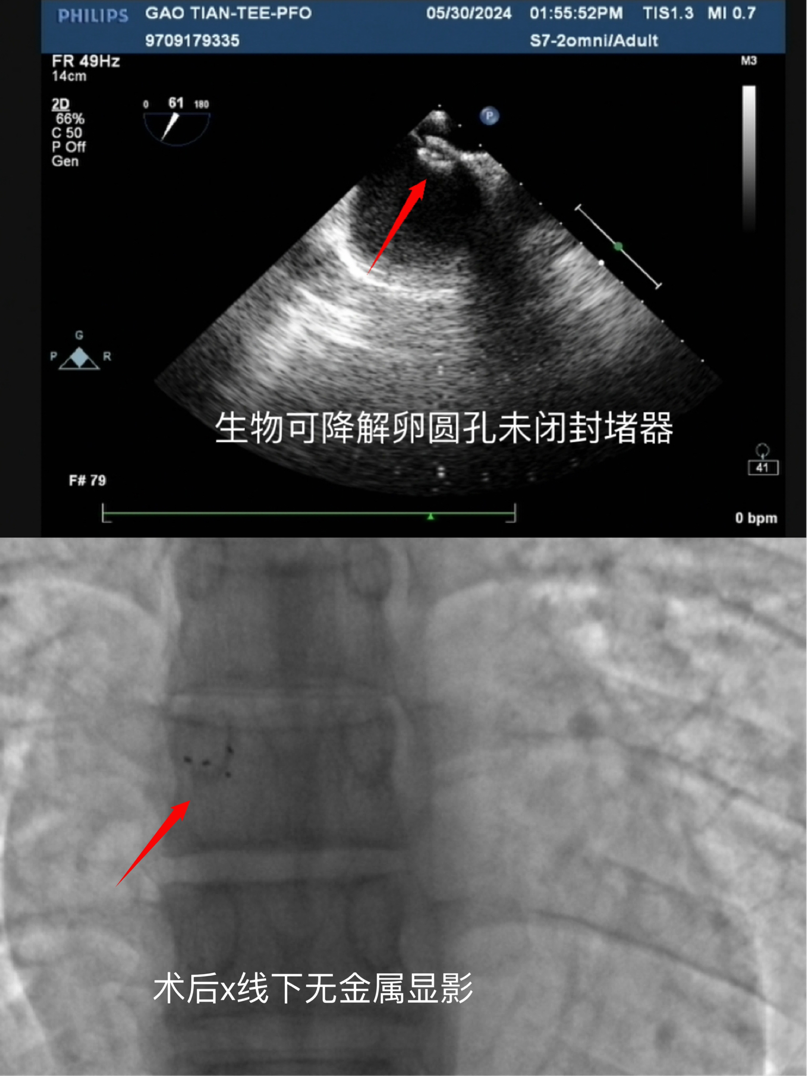

術后心臟彩超及X光顯影圖

手術過程中,先心病介入專家團隊、超聲科以及麻醉科專家團隊展現了高超的專業(yè)技能和團隊協作精神。在精確的術前評估和周密的手術計劃下,團隊成功將生物可降解封堵器植入患者心臟的卵圓孔未閉處,實現了即刻封堵,通過食道超聲驗證無殘余分流,手術圓滿結束。術后,在心血管內科全體醫(yī)務人員的協作下,患者恢復良好,頭痛癥狀逐漸減輕,目前已順利出院。